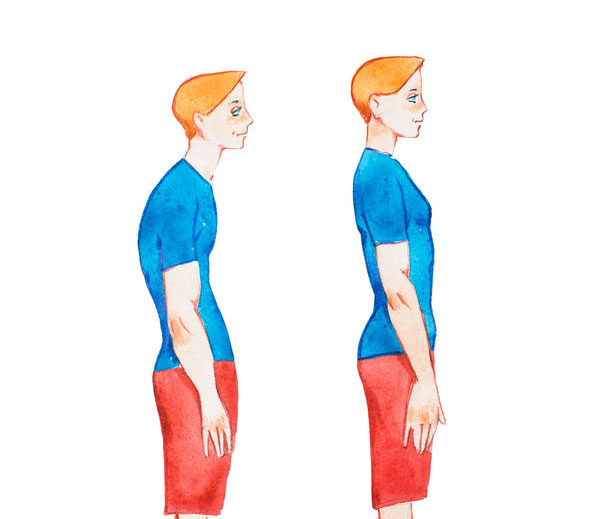

El doblarse hacia delante le llamamos cifosis. Si miramos la columna desde el lado, veremos que tiene unas curvas. Son normales, tenemos el tórax algo redondeado y la columna lumbar algo metida (todos somos un poco “culo pollo”). De este modo hablaremos de una cifosis torácica y de una “lordosis” lumbar. A los padres os preocupa la cifosis, es normal, es lo que se ve. A tu fisio le preocupará más la curva lumbar que tiene que ver en la forma que posicionas tu pelvis y afecta a la “postura global”.

Si no hay enfermedad, se trata de una cifosis flexible que trataremos con ejercicios de potenciar músculos de la espalda o incluso con psicoterapia para los casos que tenga algo que ver con inseguridad o miedo al nuevo aspecto de cuerpo adulto. Hay un truco que os funciona muy bien y que veo que evita conflictos madre-niño. Estáis ambos hartos de decir/escuchar el “ponte recto” o “saca pecho”. En vez de eso vais a recordar lo que os explico en la consulta “gira las manos”. Se trata de girar las manos hacia fuera, mucho, mucho, hasta que los pulgares casi apunten hacia atrás. Eso te hará crujir la espalda y notarás que se pone recta. Memoriza esa posición y guárdala.

Me he dado cuenta que parte de este problema es nuestra cultura de lo estéticamente deseable. El cuerpo quiere tener un tórax con volumen suficiente para los pulmones y corazón. Le da igual si es plano atrás y saliente delante o si es romo por detrás y plano por delante. Pero admitámoslo, nos gusta una espalda recta “de nadador” y un tórax algo saliente como de “estar fuerte”. Mira bien cómo es el tórax de papá o del abuelo. Tal vez el del niño sea como el de la familia, no lo olvides.